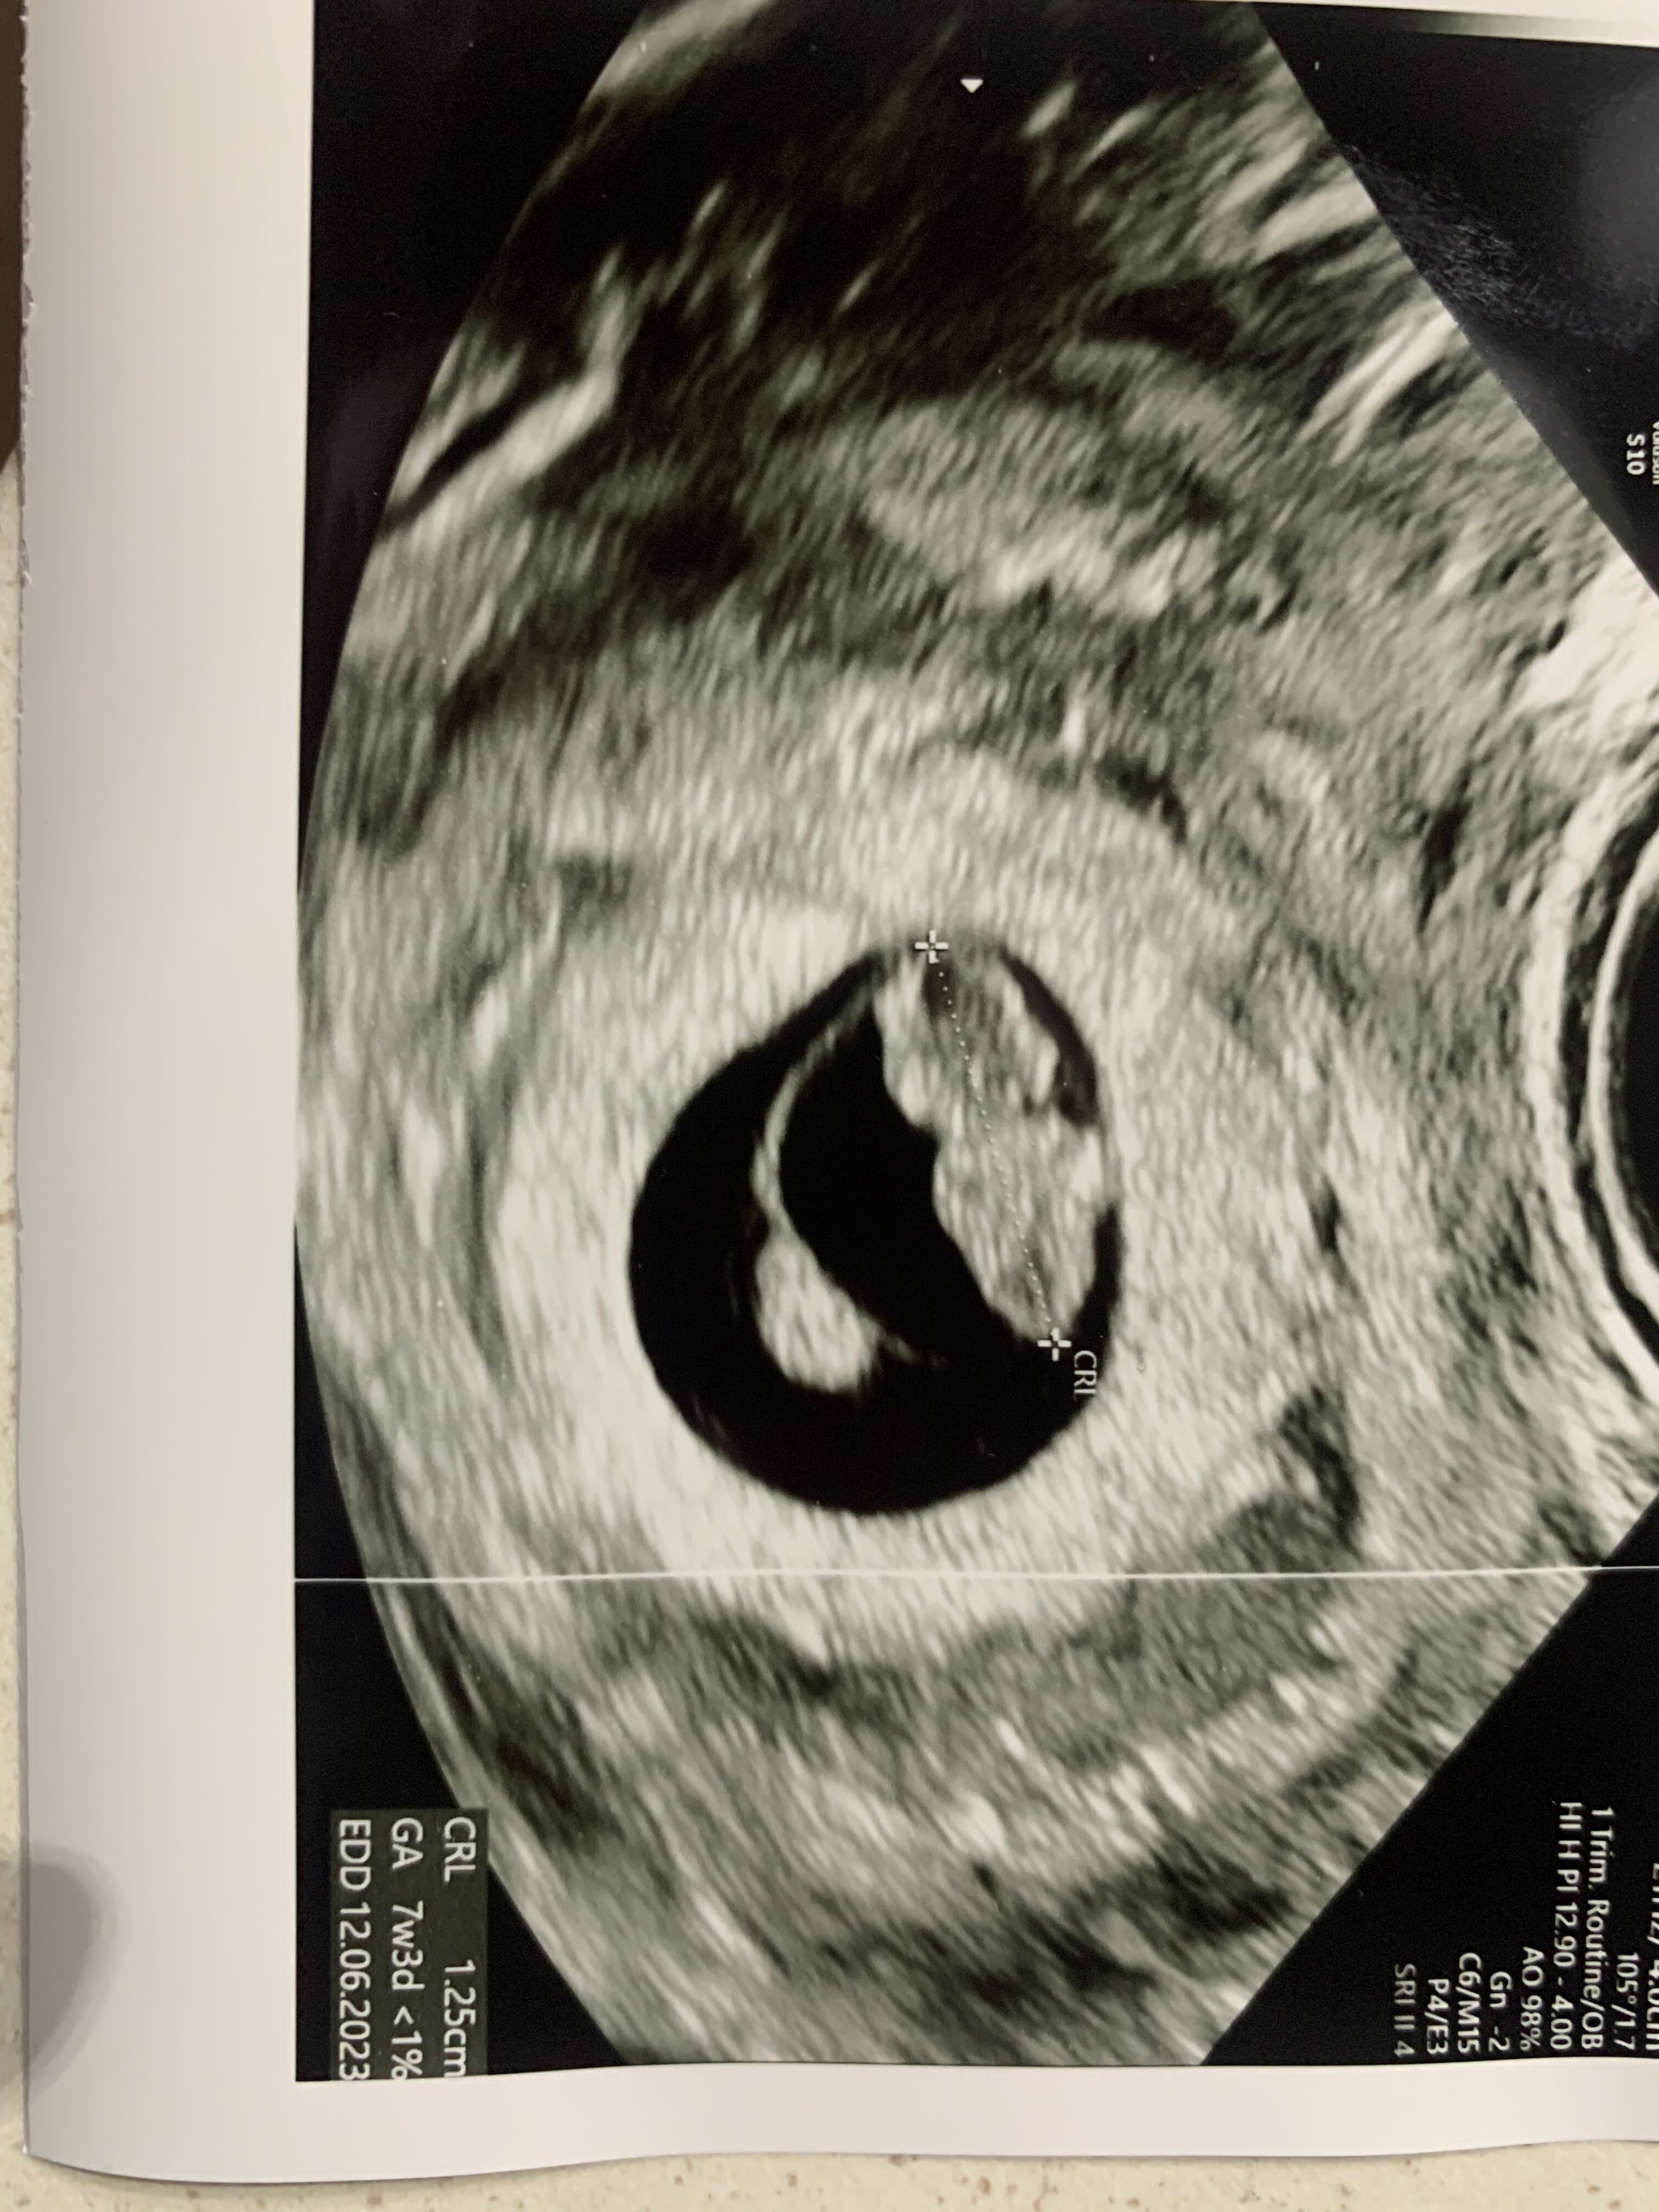

znowu mamy niespodziankę. Jutro idę sprawdzić przyrost. Beta z wczoraj 56 więc znowu bardzo wczesna ciąża, chyba owu była nawet później niż w 30dc. Może być tak że finalnie termin będzie na lipiec. W każdym razie jakoś nie umiem się cieszyć, chyba dopiero muszę zobaczyć serduszko żeby uwierzyć że naprawdę się udało. Bardzo się boję że to będzie kolejny biochem...